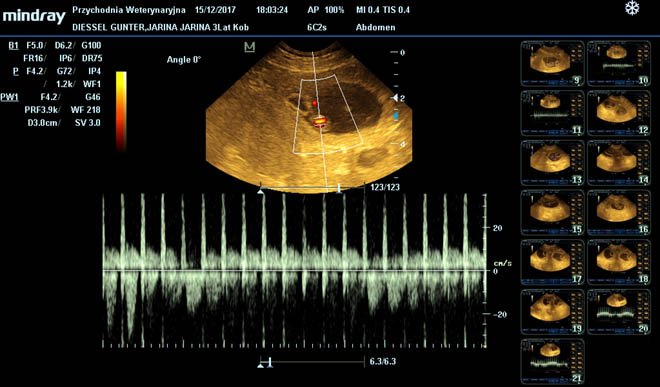

Ultraschalluntersuchung

Eine Ultraschalluntersuchung zur Feststellung der Trächtigkeit wird bei jedem Wurf durchgeführt. Es muss aber darauf hingewiesen werden, dass mit dieser Methode nicht zu 100% die Welpenzahl festgestellt werden kann.

Herzultraschall und Röntgenkontrolle

Beide Methoden werden nur bei Geburtskomplikationen angewendet. Mit dem Herzultraschall kann die Herztätigkeit der Welpen und damit deren Sauerstoffversorgung kontrolliert werden. Durch Röntgen kann die Anzahl der Welpen ermittelt werden. Für beide Methoden steht ein Tierarzt unseres Vertrauens rund um die Uhr zur Verfügung.